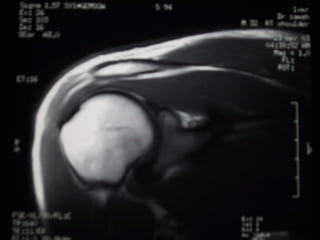

Case 5   Supraspinatus full thickness tear